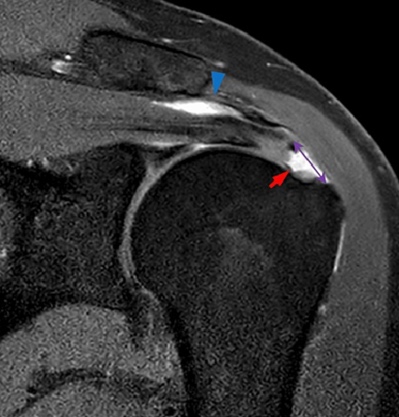

Our general doctor referred Paula to an orthopedic surgeon. He was competent to give her cortisone shots and physical therapy exercises. Nothing alleviated the pain for long. Eventually, the surgeon ordered an MRI, which revealed a torn anterior supraspinatus and its tendon. In plain English, she had a torn rotator cuff.

The repair was accomplished using arthroscopy. Screws and sutures were used to reanchor the tendon to the bone. This was done in about 1.5 hours.